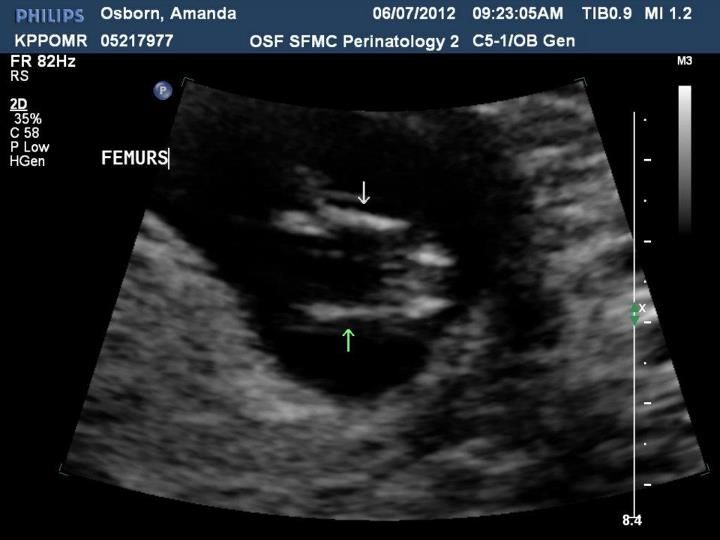

This is the one where they said BOY a week later